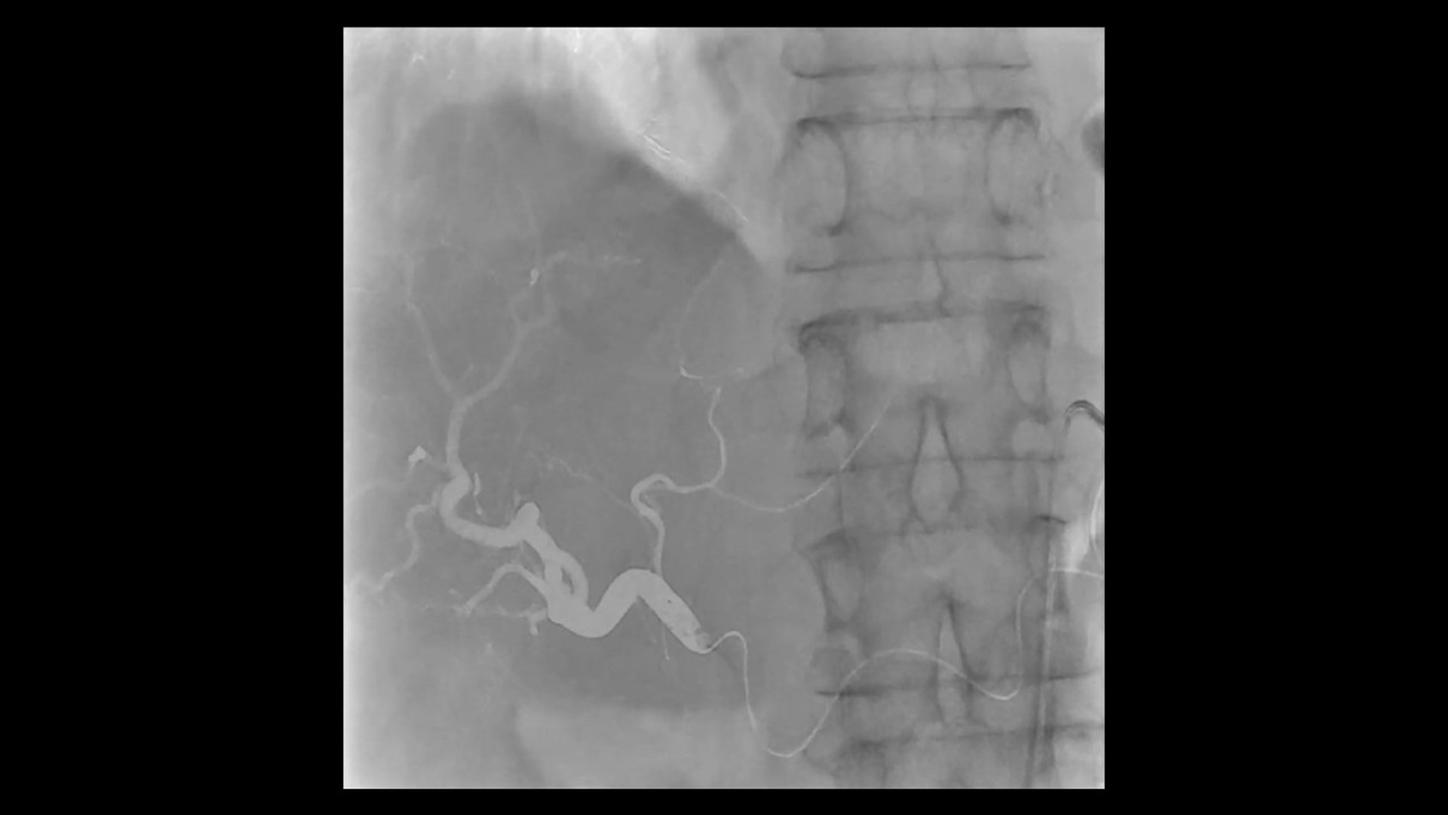

During minimally invasive procedures, it is critical to have a clear view of anatomies and devices. Yet complex imaging tasks or challenging patient conditions often impact image quality. OPTIQ AI delivers constant image quality1 defined by CNR in support of the ALARA principle, independent of patient or C-arm angulation. On top, an AI-powered algorithm reduces image noise in real time across different 2D imaging modes.

Make AI-powered imaging and clear insights your standard during interventions – with OPTIQ AI.

Future-focused IR imaging for a broad procedure mix

Discover how leading clinicians are transforming interventional radiology with Siemens Healthineers technologies. From ultra-fast 3D imaging to laser-guided needle procedures, the ARTIS icono ceiling powered by OPTIQ and syngo DynaCT are redefining what’s possible in IR. Explore real-world cases, expert insights, and the future of image-guided therapy.